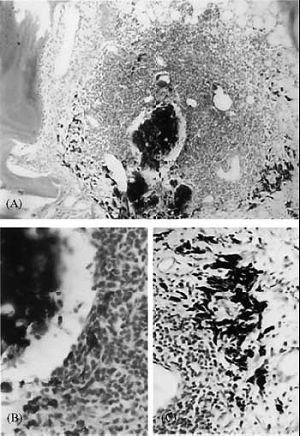

Seven root canals were filled within the canal, and two were overfilledwithAH26. In five of the root fillings con fined to the canal, no inflammatory reaction was detected, and in two cases mild lymphocytic/plasmocytic infiltration was seen. In the two overfilled cases, moderate lymphocytic/plasmocytic and granulomatous infiltration was observed around the sealer. Extracellular sealer particles were detected at the centre of the inflammatory reaction. Sealer particles were also seen in the peripheral zones of the inflammation, but in this region all the sealer particles were in the cytoplasm of macrophages. The inflammatory reaction contained no foreign body giant cells (Fig.1).

Figure 1. Periapical tissue reaction in root canal over filled with AH26.

(A) Lymphocyte, plasmacell and macrophage infiltration around sealer particles.

(B) Surplus sealer particles are surrounded by lymphocytes, plasmacells and macrophages.

(C) Peripheral parts of the inflammatory.

AH26 also initiated a chronic lymphocytic/plasmocytic inflammatory reaction around two of the seven properly filled root canals, but neither granulomatous nor necrotic tissue reaction was associated with the inflammation. It has been demonstrated that AH26 is a relatively cytotoxic sealer (Gerosa et al. 1995, Osorio et al. 1998, Telli et al.1999,Huanget al.2002) as it contains toxic epoxide bisphenol resin (Gerosa et al.1995) and releases formaldehyde during and after setting (Spangberg et al. 1993, Gerosa et al.1995, Leonardo et al.1999). Similar to Endamethasone, AH26 also initiated periapical chronic inflammatory reactions in the overfilled root canals; however, the lymphocytic infiltration did not contain foreign body giant cells.TheAH26 particles were phagocytosed by macrophages and carried to the periphery of the inflammatory reaction. This finding suggests that in the course of time, macrophages may completely clear the sealer from the overfilled area and periapical tissue may heal eventually; however, in a 3-year follow-up period in nonhuman primates (baboon), periapical tissue inflammatory reactions were still detectable when AH26 was used (Pascon et al.1991).